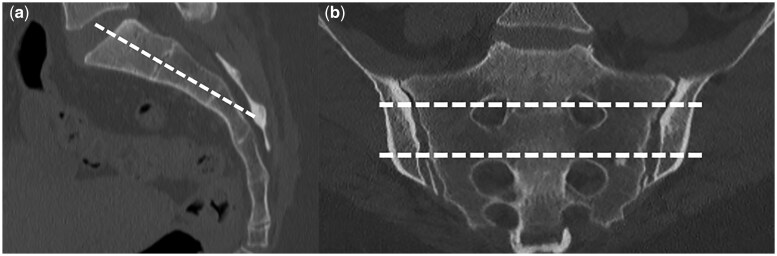

Results: All patients were female with a mean age of 34 years. BME was observed in 66% (19/29) of OCI patients. BME in OCI was mainly located in the anterior-middle quadrant (43.48%). OCI patients had significantly more than one delivery (P = 0.0094, McNemar test), even if OCI was found in four nulliparous patients (15%). OCI patients experienced significantly more pain (P = 0.0026, McNemar test).

Conclusion: OCI is an entity found in both pregnant and non-pregnant young women. SIJ BME was found in two-thirds of OCI patients. OCI is a significant cause of BME and should be carefully considered by clinicians when dealing with a patient with low back pain in order to avoid misdiagnosing spondyloarthritis in the presence of BME of the SIJ.